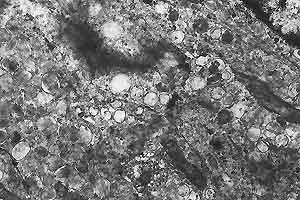

- Case 19-3. Rat A, 10200x

This electron micrograph illustrates the finer detail of the

premelanosomes as well as the multiple desmosomes between the

neoplastic cells, and absence of a basal lamina.